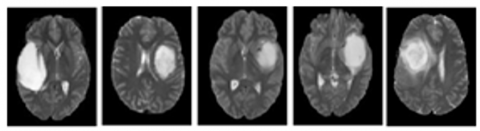

In this work, the objective is to generate a segmentation of the heterogeneous tumor region. To achieve this, two datasets were utilized, including the publicly available BRATS 2015 [31]. Furthermore, a private dataset was collected from the Civil Hospital of Setif, comprising 18 healthy and 18 unhealthy subjects. In the BRATS 2015 dataset, we specifically chose malignant tumors for segmentation and classification. A sample of the selected datasets is illustrated in Figure 2.

Figure 2. Brain tumor samples from the image dataset used in this study